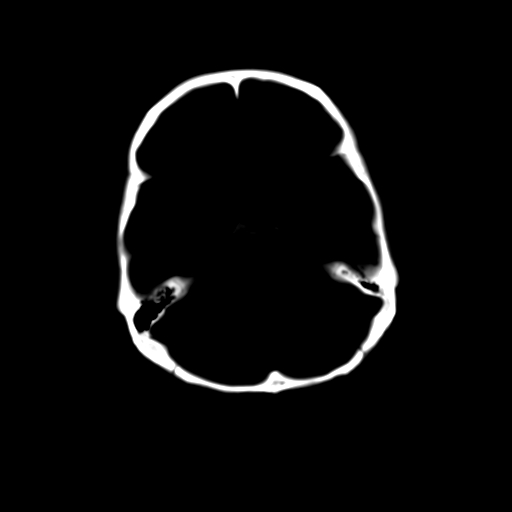

标题: CT23995:女,42岁,前额部外伤1小时,伤后头痛。 [打印本页]

女,42岁,前额部外伤1小时,伤后头痛。

颅内未见明显异常,枕骨松质骨瘤可能性大。颅骨板障起源骨瘤较常见,骨血管瘤有垂直骨针及粗大钙化,嗜酸性肉芽肿软组织有改变,典型者可见“纽扣状”死骨,年龄通常较小。

左枕骨松质骨不均匀低密度灶,边缘清楚,考虑良性松质骨性骨瘤可能性大。